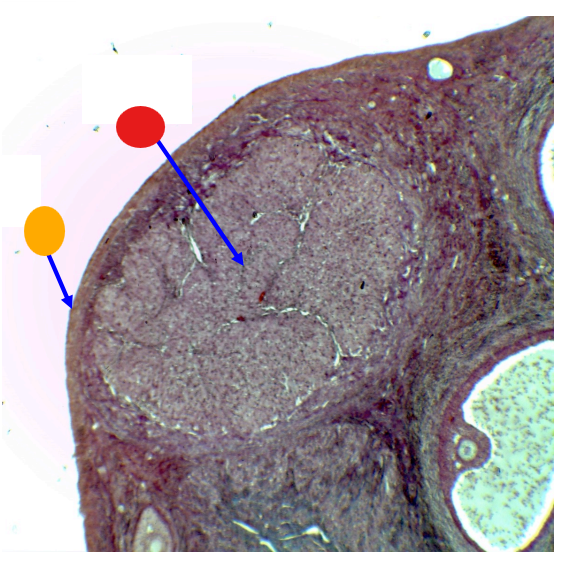

What is this

mature follicle

red

cumulus oophorus

orange

tertiary follicle

yellow

intermediate tertiary to mature follicle

red

corpus luteum

orange

tunica albuginea